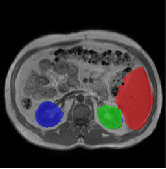

Table 2 presents an ablation study and compares SparseMamba-PCL with nine SOTA scribble-supervised methods across the three datasets. Out method achieves the highest Dice score across all the datasets, and the lowest (CHAOS) and second lowest (ACDC and MSCMRSeg) HD95 values, confirming its effectiveness in segmentation accuracy and boundary refinement. Baseline+SPOBE and Baseline+PCL improve upon the Baseline (SparseMamba), demonstrating the benefits of boundary-aware supervision and SAM-guided learning. Fig. 4 (l) compares the segmentation performance of SparseMamba-PCL with other scribble-supervised methods, showing smoother edges that precisely delineate object boundaries, unlike the jagged or blurred edges in other methods. The examples also demonstrate the consistent segmentation quality achieved by SparseMamba-PCL across ACDC, CHAOS, and MSCMRSeg, highlighting its adaptability across multiple medical domains. This adaptability and precise segmentation is crucial for accurate volumetric analysis and clinical decision-making, where even subtle boundary inaccuracies can lead to diagnostic errors. In summary, the SparseMamba-PCL architecture provides a consistent and robust improvement in segmentation metrics across diverse medical image datasets.

Refer to caption Refer to caption Refer to caption Refer to caption Refer to caption Refer to caption Refer to caption Refer to caption Refer to caption Refer to caption Refer to caption Refer to caption

(a) (b) (c) (d) (e) (f) (g) (h) (i) (j) (k) (l)

Figure 4: Qualitative comparison of weakly-supervised segmentation methods on ACDC, CHAOS, and MSCMRSeg datasets. (a) Input image, (b) ground truth, and segmentation results from (c) USTM [16], (d) Scribble2D5 [5], (e) CycleMix [26], (f) ShapePU [27], (g) S²ME [21], (h) ScribbleVC [12], (i) TDNet [30], (j) PacingPseudo [25], (k) Scribbleformer [13], and (l) SparseMamba-PCL are given.